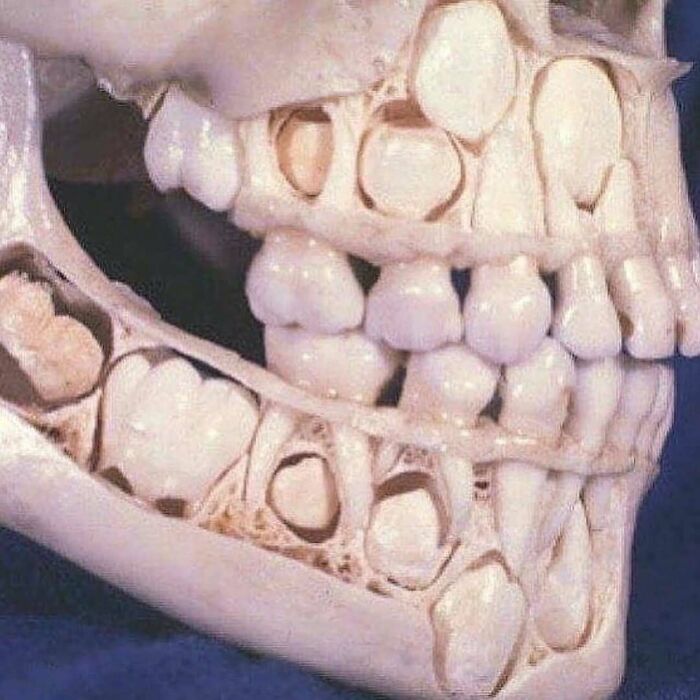

Rare case of a child suffering from a condition called hyperdontia.

Hyperdontia is a condition where an individual have supernumerary teeth or more teeth than regular that can appear in any area of the dental arch and can affect any dental organ.

According to the Canadian Dental Association (CDA), the cause of supernumerary teeth remains to be incompletely understood. But, one theory suggests that supernumerary teeth may be a result of the dichotomy of the tooth bud. Another theory proposes the hyperactivity theory which states that supernumerary teeth are formed because of local, independent, conditioned hyperactivity of the dental lamina. Heredity may also be a factor in the occurrence of these teeth particularly certain hereditary conditions like Gardner’s syndrome, Ehlers-Danlos syndrome, Fabry disease, cleft palate and lip, cleidocranial dysplasia.

The treatment for hyperdontia is dependent on the type and position of the supernumerary tooth and how it affects the adjacent teeth and may require removal.